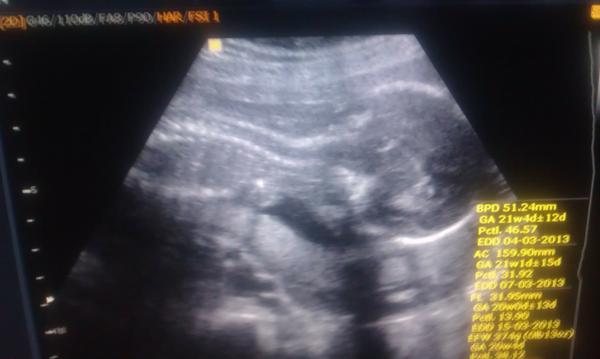

ahojte dievčatá....takže zajtra ideme na morfo ultrazvuk....sme na konci 21tt, tak by sa naše babatko mohlo aj ukázať...čo s atýka mojho zdravotného stau som na otm zle, v sobotu som musela ist na pohotovosť, nakoľko mi bolo opat velmi zle ako pred vyše dvoma týždnami ked som celu noc zvracala a rano som mužovi odpadla...ked sa to v tuto sobotu opakovalo, aj ked to nebolo až také zle tak som už isla☹výsledok - krv vporiadku, babtko vporiadku, sono žaludka, oblíčiek a tak dalej, vporiadku, len v moči som mala nejaku infekciu tak sommusela brat antibiotika a som až do konca tehu na diete...ale už je to lepšie...na taketo bolesti ako som mala neprajem nikomu...pri Samkpovi som ani nevedel aže osm tehu a teraz sa mi to riadne ohlaasuje....inak babtko denne tancuje ako divé, takže to som velmi rada....zajtra sa ozvem ako sme dopadli....zatial sa majte...tým co ste už tehu prajem bezproblémove tehu a snažilkám veselé snažilkovanie🙂